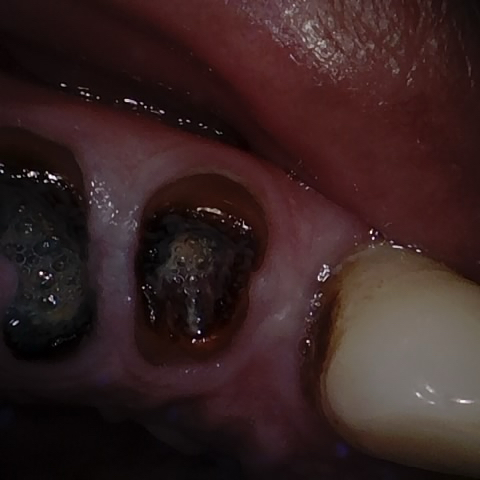

Incorrect Quality Level

The reference annotation for this image is

None

.

Please select the correct quality level.

Annotated as "Good"